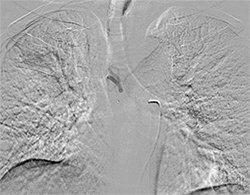

Procedure in which the blood supply of abnormal and diseased part of lung is blocked with medicine. A small puncture is made in blood vessel of thigh region with needle through which wire passed and sheath placed. Angiography done with catheter under X-ray guidance.